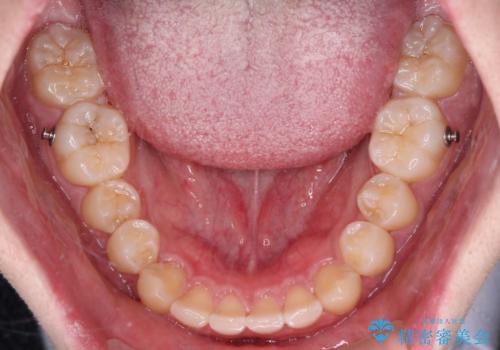

- 矯正装置

- インビザライン

- 前方に傾斜した前歯を気にして来院された患者様です。

強く食いしばってしまう癖があり、下顎前歯に押し出されて上顎前歯が前方へ斜めに突き出している状態でした。

IPR(歯と歯の間を削る)を多用して、インビザラインにて矯正治療を行うこととしました。

口元を引っ込めるためのゴムかけを頑張っていただき、満足のいく上顎前歯の傾斜へ改善することができました。